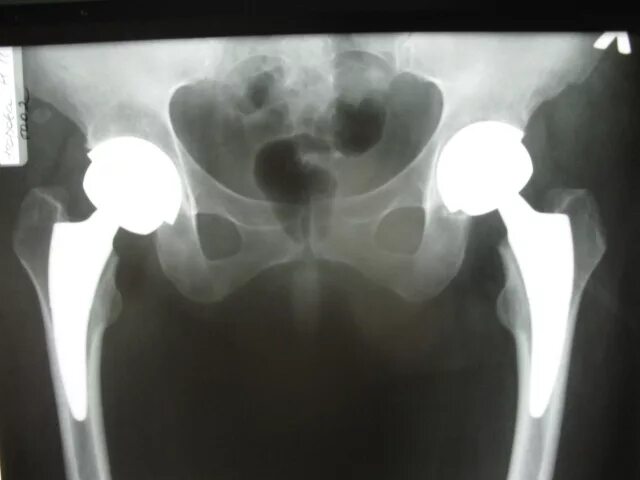

Нестабильность тазобедренного сустава